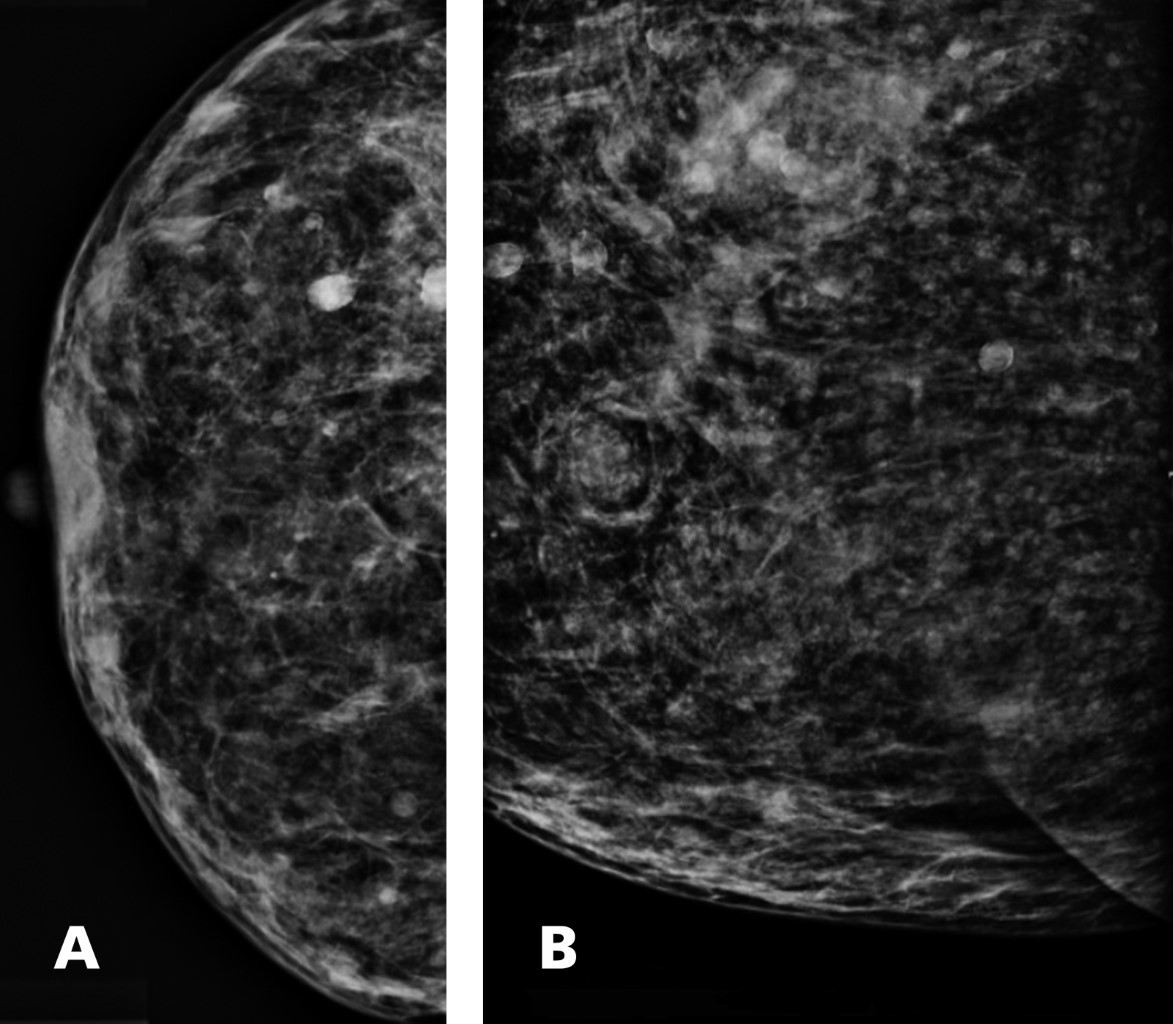

La mastografía evidencia aumento de la densidad por la presencia de múltiples nódulos hiperdensos de diversos tamaños con extensión hasta la región retromamaria y cola de Spencer, algunos de los nódulos con calcificación discontinua de sus bordes. BIRADS 0 (Figura 1).

Figura 1